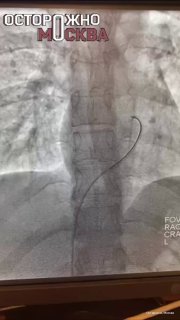

Подкожный контрацептив из руки перекочевал в лёгкое москвички.

36-летняя женщина обратилась к врачам, когда стержень Импланон перестал прощупываться в руке. Оказалось, он мигрировал в лёгкое.

Имплант успешно удалили.